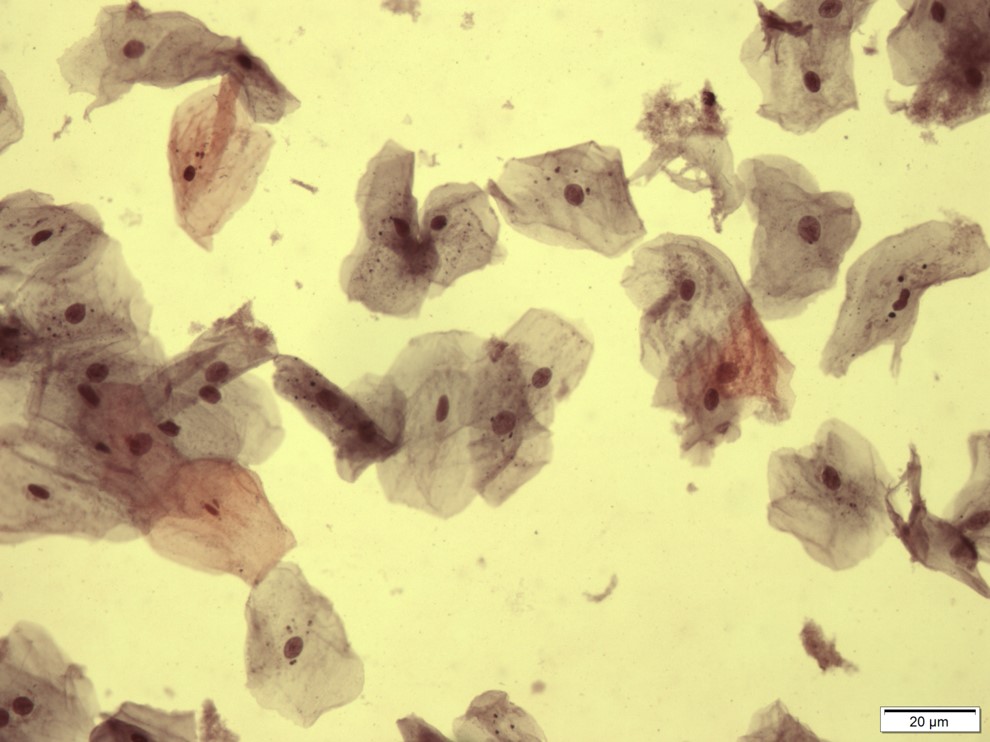

Exemplo de amostra adequada

Para essa avaliação, caracterizam-se as 100 primeiras células bem distendidas e não sobrepostas avaliadas num aumento de 40 vezes.

As células são então classificadas com relação ao estrato epitelial ao qual provavelmente pertenciam conforme a sua morfologia: células superficiais anucleadas ou com núcleo, intermediárias e parabasais. A seguir detalharemos características específicas de cada uma delas.

Células Superficiais com Núcleo

Células grandes e poligonais, com citoplasma abundante, usualmente acidófilo, podendo ser cianófilo. Seu núcleo é picnótico e hipercromático. Sua coloração compreende do laranja-avermelhado até o castanho-pálido.

Células Intermediárias

Células com núcleos pálidos vesiculares maiores comparando-se com células superficiais. O citoplasma pode conter partículas de glicogênio, usualmente apresenta-se cianofílico podendo ser acidófilo.